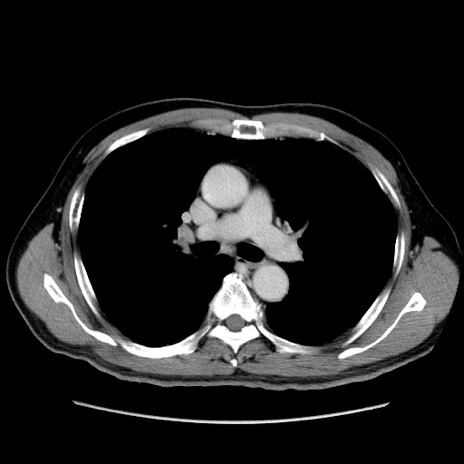

症例34(横断像)

【症例】60歳代 男性

【主訴】右鼠径部膨隆

【現病歴】1年程前より右鼠径部膨隆あり。自己にて還納可能だったため放置していた。3時間前より右鼠径部の脱出を認め、還納困難となり受診。

【既往歴】高血圧

【身体所見】右鼠径部に小児頭大の膨隆あり。弾性硬であり、用手還納は困難。左鼠径部にも膨隆を認める。脱出はなし。

【データ】WBC 15500、CRP 測定なし